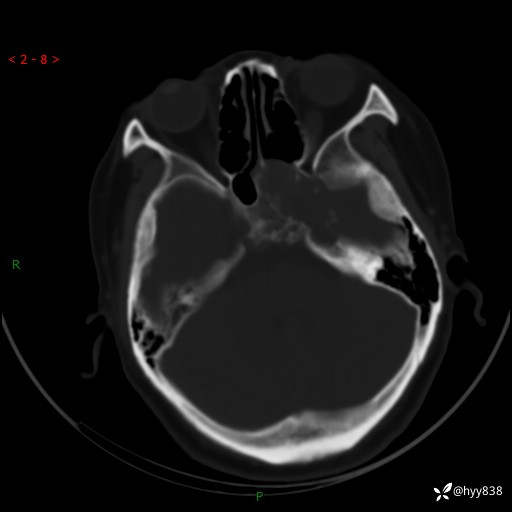

颅脑CT平扫

老年女性,视力下降3年。鞍区钙化性肿块,鉴别诊断有哪些---(有结果)

简要病史:患者3年前无明显诱因左眼出现视力下降,出现视物模糊,无头痛,无头晕,无恶心、呕吐,无意识障碍,无肢体麻木及抽搐,无心慌、胸闷,无腹痛、腹胀等不适,无旋地转感。个月前右眼视力下降,患者视物模糊逐渐下降,自诉看东西有雾感。在当地医院眼科就诊,症状无好转,行头部MR提示:鞍区肿物。现患者为求诊治来我科就诊,在当地市中医医院行头部CT:提示鞍区占位。患者现求进一步诊治来我院就诊,门诊以“鞍区肿物”收入我科。 患病以来,患者精神、饮食、睡眠尚欠佳,大小便如常,体力体重无明显变化。

临床诊断:鞍区肿物